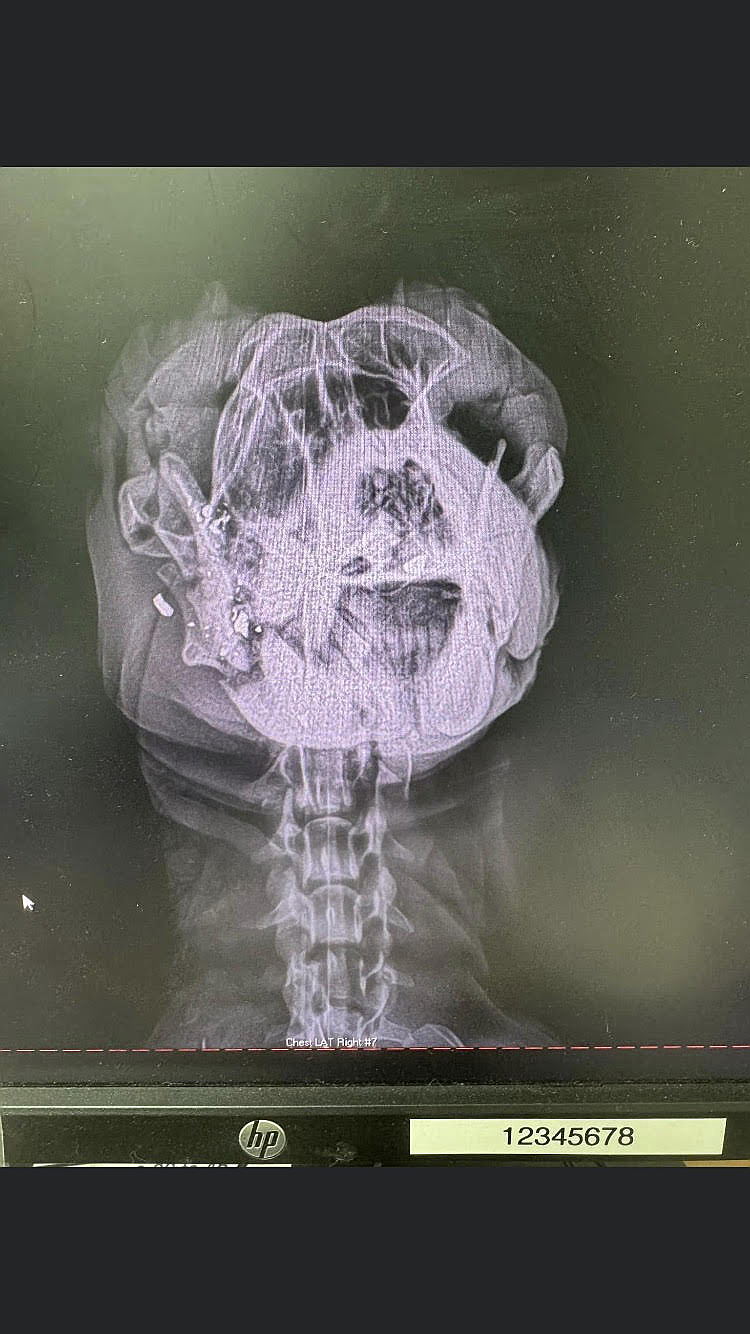

Animal Control received a report of a dog found wandering with a clear head wound from a bullet. But no one could find the dog. The cold, the snow, the misery set it. And no one could find her.

Then another call came in about the same dog in the same location. Where had she been? How had she survived? Who did this?

Thankfully, she was found and rushed to the hospital to receive treatment but she has a journey to go to be out of the woods.

Infection has set in and she will need surgery again very soon - and will likely lose teeth. She remains sweet and kind and wiggy despite her odds and we are desperate to get her in shape to be loved forever.